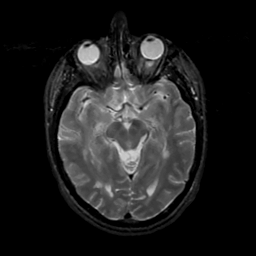

MR Study #8, March 31, 1991 -- Slice #21

[Home][Help][Clinical][Tour 1][Tour 2] Slice 21